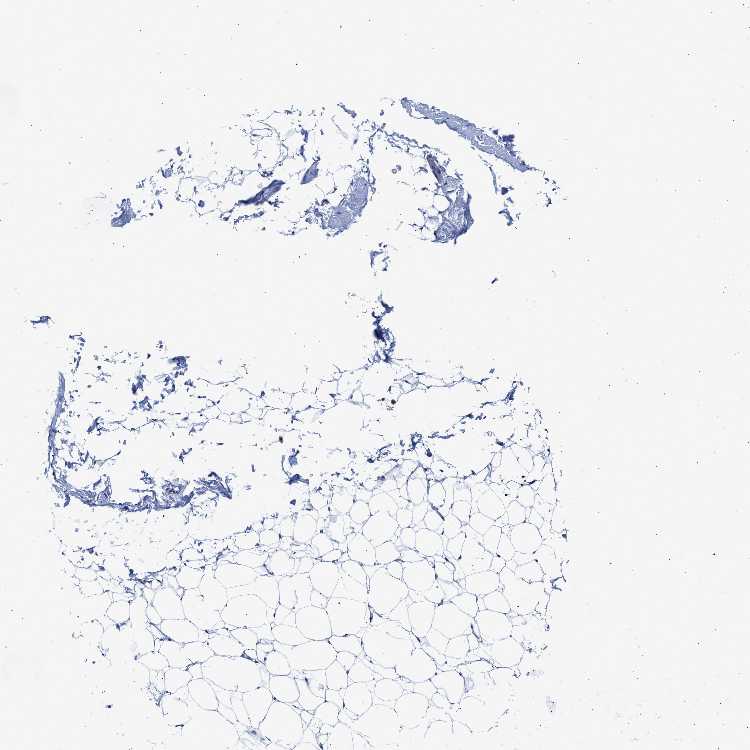

SOFT TISSUE 2 - Antibody stainingi

Antibody staining in the annotated cell types in the current human tissue is reported as not detected, low, medium, or high, based on conventional immunohistochemistry profiling in selected tissues. This score is based on the combination of the staining intensity and fraction of stained cells.

Each image is clickable and will lead to virtual microscopy that enables deeper exploration of all samples and also displays staining intensity scores, fraction scores and subcellular localization as well as patient and tissue information for each sample.

Antibody HPA021165Antibody HPA021753Antibody HPA021760

Fibroblasts Not detectedNot detectedNot detected

Peripheral nerve Not detected-Not detected